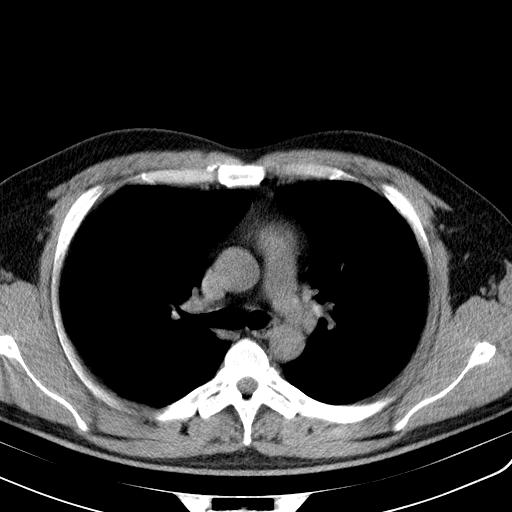

一周后复查胸片基本正常

经一周抗炎抗病毒治疗复查胸片示病变大部吸收,基本恢复正常,未做气管镜检查,考虑为炎性变或霉菌感染。